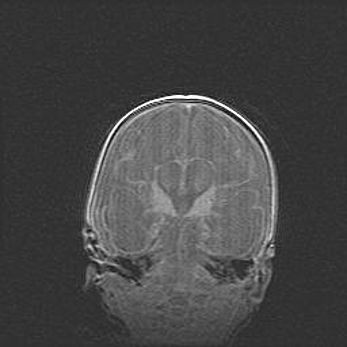

Лейкомаляция с кистозно-глиозной дегенерацией головного мозга.

Возраст: 2 месяца 25 дней

Вес: 6400 г

Окружность головы: 40 см

Срок гестации: 41 неделя

Лейкомаляцию относят к ишемически-гипоксическим повреждениям головного мозга, диагностируемым у новорожденных. При лейкомаляции в головном мозге обнаруживают очаги некроза, возникшие после тяжелой гипоксии и нарушения кровотока. В процессе морфогенеза очаги проходят три стадии: 1) развития некроза, 2) резорбции и 3) формирования глиозного рубца или кисты. Перивентрикулярная лейкомаляция (ПЛ) встречается примерно в 12% случаев среди новорожденных, обычно – у недоношенных детей, причем, частота ее зависит от массы, с которой младенец появился на свет. Наибольшее число малышей страдает лейкомаляцией, если масса при рождении 1500-2500 г.